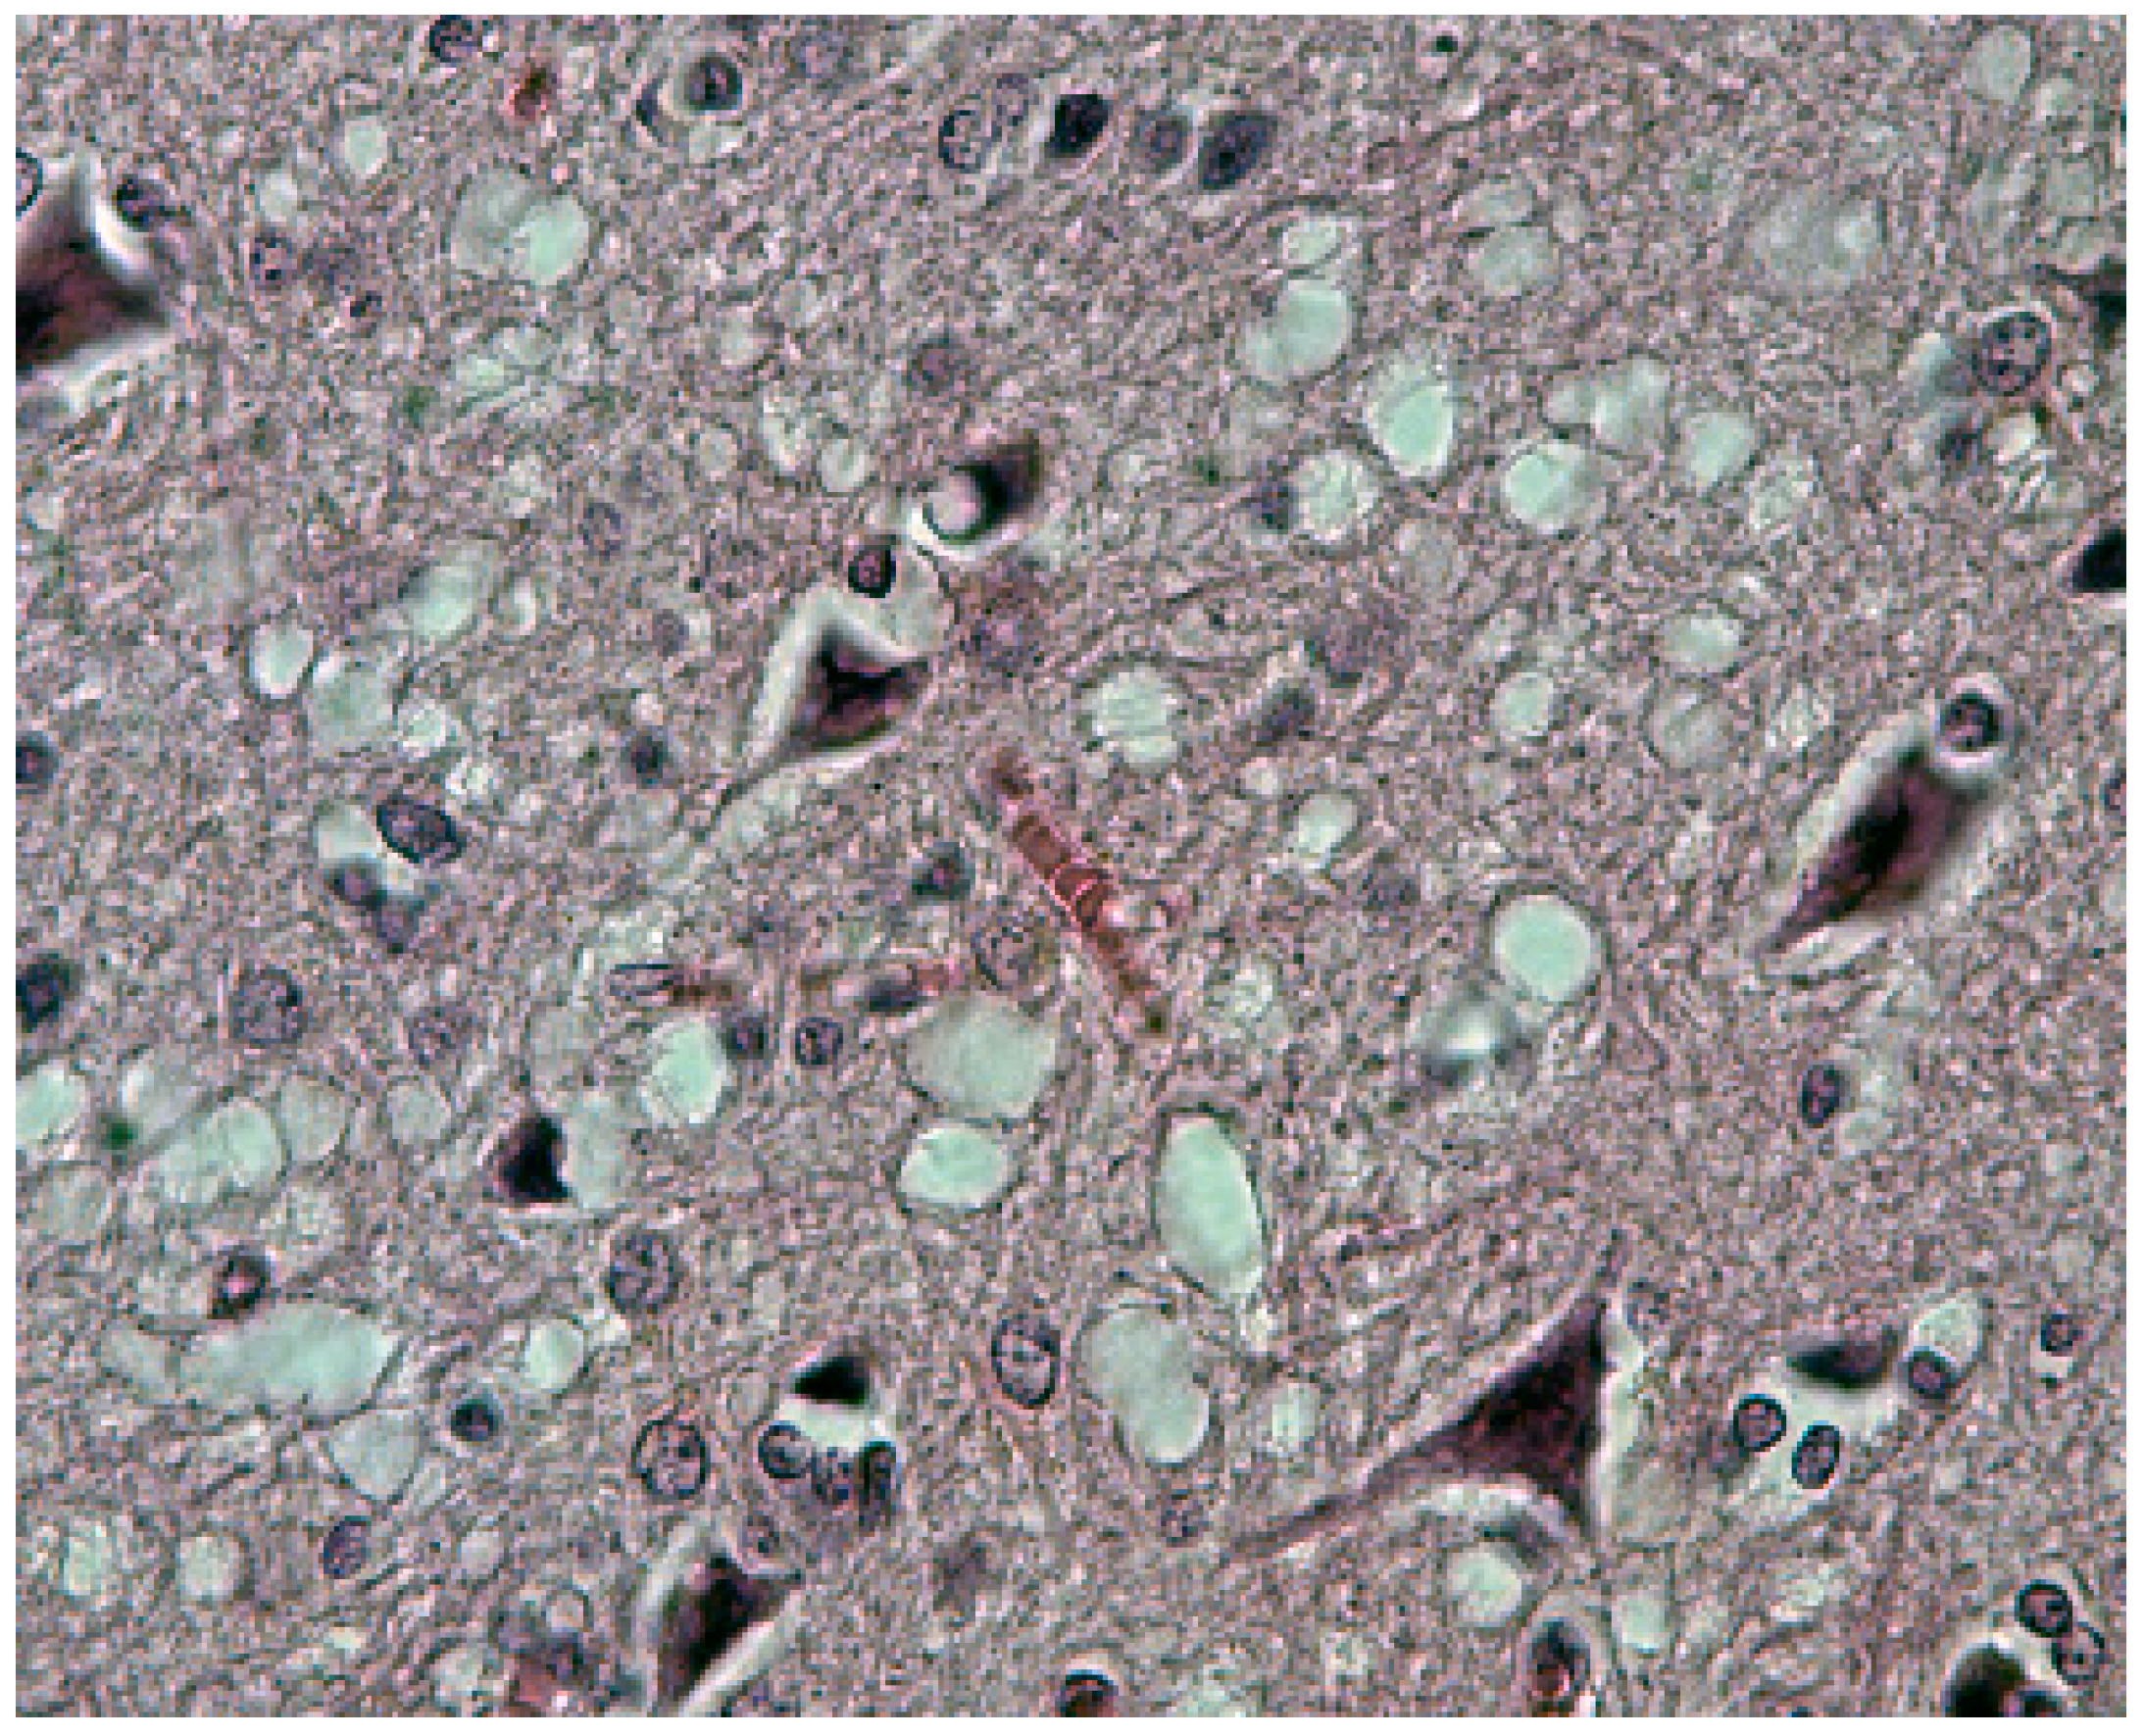

Neuronophagia was observed. A few binucleated neurons were visible, and torpedo formation was noticed in the Purkinje cell layer, along with empty baskets that marked the presence of absent Purkinje cells. In the medulla, neurons of the vestibular nuclei and the lateral cuneatus were frequently affected; the spinal nucleus of the trigeminal nerve and nuclei of VIth, VIIth, and motor nucleus of the VIth cranial nerves were affected less frequently, while nuclei of the XIIth cranial nerve, the dorsal nucleus of Xth cranial nerve, and nucleus ambiguous were relatively spared. In the cerebral cortex, the deeper layers were affected more than the superficial layers, and neurons in the hippocampal formation were normal. In the cerebellum, the paleocerebellar structure (vermis and flocculo-nodular lobe) was most severely affected, and spinal cord pathology was most severe in the corticospinal and spinocerebellar tracts. Astroglial (Figure 15a,b) and microglial proliferation was widespread; the latter formed rosettes and appeared as rod or amoeboid types or as macrophages (gitter cells). Myelin degradation was observed in 10 of 12 cases. Interestingly, the significance of vacuolar changes was not appreciated by Klatzo et al. [124,125], but “small spongy spaces” were noted in seven of 13 cases studied by Beck and Daniel [106,107,108,109,110].

Figure 15.

(a) Proliferation of GFAP-positive astrocytes against the background of spongiform change; (b) amyloid plaque stained with Alcian blue surrounded by an astrocyte. Courtesy of D. Carleton Gajdusek.